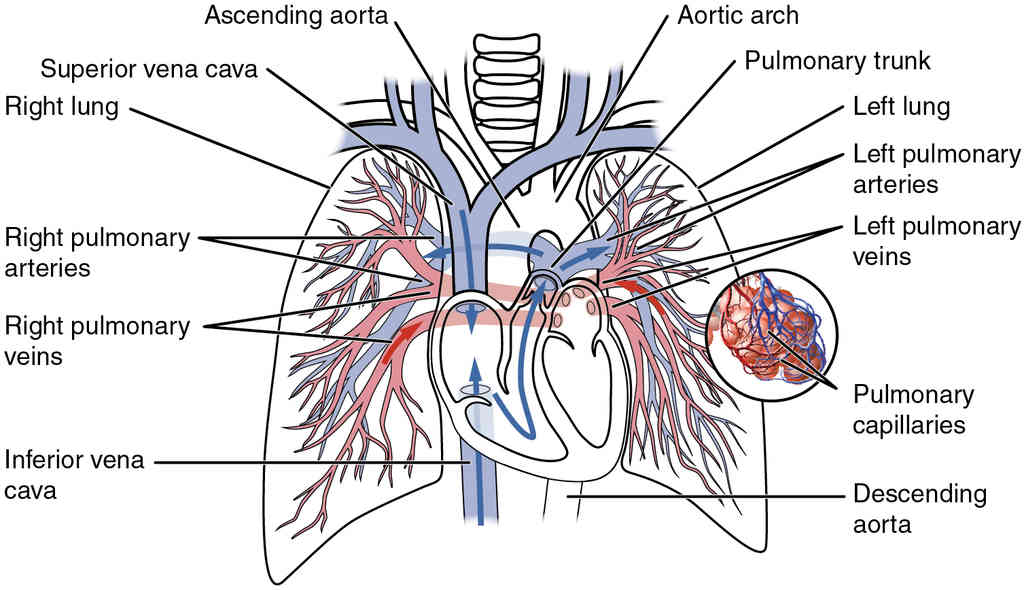

This page is under construction. For now, it is just a resource of the images found in the OpenStax Anatomy and Physiology Handbook. It wil slowly change into a revision tool. Each slide has a number. Use this to refer to the slide. When completed, it will have an unlabelled section, with labelled slides in parallel. On the unlabelled slides, write your answer and use the labelled slide to assess yourself. Keep track by also noting the number on each slide. Improvement at each attempt is important, more so than full marks on a first attempt.